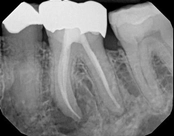

Non-surgical root canal treatment:

Before

After

6-month follow-upThe patient presented with mild pain, a cavity, and a broken filling was evident. After performing diagnostic testing, the diagnosis was: irreversible pulpitis, symptomatic periradicular periodontitis. Root canal therapy was done and the tooth healed well and is still functioning.